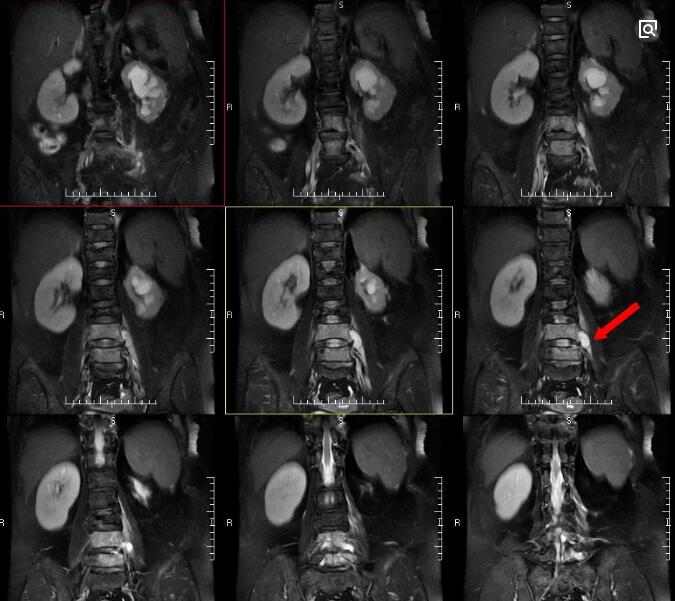

②结核多侵犯松质骨,腰椎结核多发于成年人腰痛是腰椎结核常见的症状,疼痛的性质多为钝痛或酸痛,伴有压痛及叩击痛,在劳累、咳嗽、睡前疼痛加重。上腰椎结核可有大腿痛,下腰椎结核可有坐骨神经痛,这是由于结核脓肿、肉芽组织及坏死的椎间盘或死骨向后突入椎管内,使脊髓或神经根受到压迫或刺激时,可出现放射痛。>>>请医生帮我看一下片子

脊柱畸形:当病变发展到一定程度后,由于椎体破坏塌陷与变形,导致腰椎明显后突畸形,侧突畸形极少见。隆起处多伴有明显之压痛及叩击痛。

寒性脓肿:寒性脓肿对于腰椎结核的诊断有重要意义。因脓肿形成缓慢,且无急性炎症特征,故称为“寒性脓肿”。脓汁一般稀薄呈米汤样,内含大量结核性肉芽组织、干酪样物质、坏死椎间盘组织和死骨等。腰椎结核的寒性脓肿多位于一侧或两侧的腰大肌,可引起腰大肌刺激症状,导致髋关节屈曲挛缩畸形、托马斯征阳性;亦可沿腰大肌流注到两侧髂窝、腰三角、股三角处,脓肿破溃后,形成经久不愈的窦道。如继发感染,则伴有急性化脓性炎症特征。